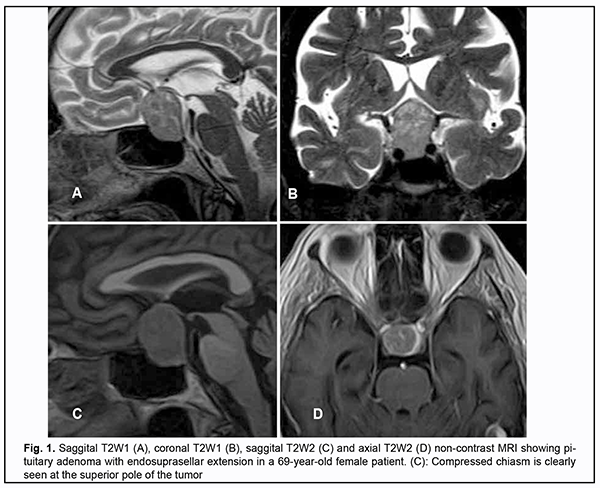

Introduction Skull-base tumors (SBTs) of the middle and anterior fossae typically cause mass effect on the optic nerve/chiasm complex. The most common of these neoplasms are pituitary adenomas, meningiomas and craniopharyngiomas [1, 2, 3, 4]. Chiasmal compression is accompanied by a gradual decrease in visual acuity, bitemporal visual field defects and development of primary descending optic atrophy (OA) [5, 6]. Clinical manifestations of SBTs vary and depend on tumor involvement, nature of growth pattern, and rate of growth. Impaired visual functions are observed in 67.8-83% of patients. Specifically, reduced visual acuity and visual field impairment have been found in 38-68.5% and 68-70%, respectively, of patients [5, 7, 8, 9]. 30-88.9% of cases manifest loss of visual acuity or visual fields [5, 9, 10]. Late-diagnosed but mostly benign processes causing compression of the optic nerve/chiasm complex may result in temporary or permanent visual function loss leading to visual disability. Prolonged chiasmal compression results in the development of OA in 26.7% to 72% of patients, leading to blindness in 3.5% to 25% of cases [4, 10, 11, 12]. Significant or rapidly progressive loss of visual acuity and/or visual fields in the presence of a small tumor may suggest malignancy. Despite progress in neuroimaging techniques, the number of new annually registered cases of primary optic atrophy (OA) associated with SBT and partial or complete loss of visual acuity and/or visual fields, is steadily increasing, making the issue increasingly important [5, 10, 12]. The purpose of the study was to investigate neuroophthalmological symptoms in patients with skull-base tumors. Material and Methods This retrospective study included the records of 500 patients (1000 eyes; 270 (54%) women and 230 (46%) men; aged 14 to 74 years; mean age, 51 ± 0.8 years) who received treatment for SBT and loss of visual acuity and/or visual fields at the Transsphenoidal Neurosurgery Department, Romodanov Neurosurgery Institute, during the period from 2017 through 2019. The inclusion criterion was surgical evidence of SBT. Patients underwent clinical and neurological, eye, and otoneurological examination (a routine otoneurological examination with assessment of cranial nerve function). Instrumental and laboratory studies were conducted. Neuroimaging included sella turcica X-ray study with AXIOM Iconos R100 (Siemens) or Radrex-I (Toshiba) in 72 patients, brain magnetic resonance imaging (MRI) with a 1.5-T MRI system (Intera 1.5T/I system, Philips Medical Systems, Best, the Netherlands) in all patients, and computed tomography (CT). The MRI of brain and pituitary gland were obtained using T1-weighted image (WI) and T2WI. Neuro-ophthalmic examination included best-corrected visual acuity assessment, biomicroscopy, static automated and kinetic perimetry, and direct and indirect ophthalmoscopy. Best-corrected visual acuity was classified as normal (1.0), mild impairment (0.7-0.9), moderate impairment (0.4-0.6), severe impairment (0.1-0.3), and very severe impairment (< 0.1). Static automated perimetry (SAP) was performed with the Centerfield 2 Perimeter (Oculus, Wetzlar, Germany) using the neurological 30-2 threshold test program and Neuro screening program. Aside from defect localization, the arithmetic mean of the sensitivity loss, the mean defect (MD), was used to assess visual field loss severity. Visual field loss severity was classified as “no visual field loss” (Grade 0; normal visual field), mild visual field loss (Grade 1; MD, –2 dB to –4 dB), moderate visual field loss (Grade 2; MD, –4 dB to –12 dB), severe visual field loss (Grade 3; MD, –12 dB to –20 dB), and very severe visual field loss (Grade 4; MD, worse than –20 dB). The visual field loss was classified as very severe if it was not possible to assess visual fields due to the extremely poor visual function. A chiasmal syndrome was considered symmetric if both eyes had the same grade of visual field loss. In addition, a chiasmal syndrome was considered asymmetric if the difference between eyes in grade of visual field loss severity was 1, and it was considered markedly asymmetric if the difference was 2 or greater. Eye movements in each of the four directions of gaze were assessed. Visual acuity was assessed with a diaphragm if there was mydriasis caused by oculomotor nerve palsy. This study followed the ethical standards stated in the Declaration of Helsinki and was approved by the Local Ethics Committee of the Romodanov Institute. Written informed consent was obtained from all individuals enrolled in the study. Results are presented as the mean and standard deviation (M ± SD). Student’s unpaired t test was used to determine differences between independent groups. The level of significance p ≤ 0.05 was assumed. Results and Discussion Loss of visual acuity and/or visual fields was found in 500 (100%) patients. Pituitary adenoma (PA) was the most common tumor-causing loss of visual acuity or visual fields (420 patients; 84%; Fig. 1), followed by sella turcica meningioma (35 patients; 7%; Fig. 2), craniopharyngioma (33 patients; 6%; Fig. 3), chiasmal glioma (8 patients; 2%), germinoma and teratoma (4 patients; 1%). There was surgical evidence both of suprasellar extension of the SBT and of compression of the optic nerve/chiasm complex in all patients.

All the 420 patients with PA exhibited loss of visual acuity in one or two eyes: in 96 (22.9%%) patients, only one eye had a VA lower than 1.0; in 268 (63.8%), both eyes had a VA lower than 1.0; in 32 (7.6%), one eye had a VA lower than 1.0, and another, a VA lower than 0.1; in 24 (5.7%), both eyes had a VA lower than 0.1. Best-corrected visual acuity was normal (1.0) in 96 (11.4%) eyes, mildly impaired (0.7-0.9) in 224 (26.6%) eyes, moderately impaired (0.4-0.6) in 226 (26.9%) eyes, severely impaired (0.1-0.3) in 214 (25.5%) eyes, and very severely impaired (< 0.1) in 80 (9.6%) eyes. In addition, 70 eyes (8.3%) were blind and 5 patients were bilaterally blind. Static perimetry found no changes in 43 (5.2%) eyes. Temporal hemianopia (either complete or partial) only was the commonest field defect (385 eyes; 45.9%), followed by temporal hemianopia with central scotoma (205 eyes; 24.6%), central scotoma only (58 eyes; 6.9%), and residual visual field in the nasal inner quadrant, with a loss of central vision (79 eyes; 9.5%). Visual field was not measurable due to extremely low visual function in 70 (8.3%) eyes. Loss of sensitivity to light was classified as mild in 132 (15.7%) eyes, moderate in 416 (49.5%) eyes, and severe and very severe in 174 (20.7%) eyes and 75 (8.9%) eyes, respectively. No loss of sensitivity to light was seen in 43 (5.1%) eyes. Ophthalmoscopy found primary descending OA in 212 (50.5%) patients. Of these, 188 patients (376 eyes) exhibited bilateral OA, and 24 patients (24 eyes), unilateral OA. Symmetric, asymmetric and markedly asymmetric chiasmal syndrome was found in 268 (63.8%), 114 (27.1%), and 38 (9.1%) patients, respectively. Ocular motility disorders (OMD) were found in 34 (8.1%) patients. Of these patients, 6 (17.6%) had isolated unilateral CNIII (oculomotor nerve) palsy, 19 (55.9%) had isolated unilateral CNVI (abducens nerve) palsy, and 9 (26.5%) had combined oculomotor and abducens nerve palsy. Sella turcica meningioma was found in 35 (100%) patients. Of these, 8 (22.9%) had the tumor with optic canal involvement. In addition, the commonest complaint was gradually decreased vision for 3 months to 2 years. Visual acuity loss was mostly asymmetric: in 15 (42.9%) patients, one eye had a VA of 1.0, and another, a VA lower than 1.0; in 9 (25.7%), both eyes had a VA lower than 1.0; in 8 (22.9%), one eye had a VA of 1.0, and another, a VA lower than 0.1; and in 3 (8.6%), one eye had a VA lower than 1.0, and another, a VA lower than 0.1. Best-corrected visual acuity was normal (1.0) in 23 (32.9%) eyes, mildly impaired (0.7-0.9) in 11 (15.7%) eyes, moderately impaired (0.4-0.6) in 9 (12.8%) eyes, severely impaired (0.1-0.3) in 17 (24.3%) eyes, and very severely impaired (< 0.1) in 10 (14.3%) eyes. Temporal hemianopia (either complete or partial) only was the commonest field defect (23 eyes; 32.9%), followed by temporal hemianopia with central scotoma (13 eyes; 18.6%), residual visual field in the inner half (10 eyes; 14.3%), residual visual field in the outer half (5 eyes; 7.1%), nasal hemianopia (4 eyes; 5.7%), lower hemianopia (2 eyes; 2.9%), and central scotoma only (1 eye; 1.4%). In addition, no visual field defect was found in 11 (15.7%) eyes. Visual field was not measurable due to extremely low visual function in 1 (1.4%) eye. Loss of sensitivity to light was classified as mild in 22 (31.4%) eyes, moderate in 9 (12.9%) eyes, and severe and very severe in 13 (18.6%) eyes and 15 (21.4%) eyes, respectively. No loss of sensitivity to light was seen in 11 (15.7%) eyes. Ophthalmoscopy found OA in 31 (88.6%) patients. Of these, 28 patients (28 eyes) exhibited unilateral OA, and 3 patients (6 eyes), bilateral OA. Symmetric, asymmetric and markedly asymmetric chiasmal syndrome was found in 3 (8.6%), 9 (25.7%), and 23 (65.7%) patients, respectively. Ocular motility disorders were found in two patients. These two had isolated unilateral partial CNIII palsy. Among the 33 patients with supradiaphragmatic craniopharyngioma, symmetric chiasmal syndrome was the most common (19 patients; 57.6%), followed by asymmetric (8 patients; 24.2%) and markedly asymmetric (6 patients; 18.2%) chiasmal syndrome. In 12 (36.4%) patients, only one eye had a VA lower than 1.0; in 11 (33.3%), both eyes had a VA lower than 1.0; in 3 (9.1%), one eye had a VA of 1.0, and another, a VA lower than 0.1; in 4 (12.1%), one eye had a VA lower than 1.0, and another, a VA lower than 0.1; and in 3 (9.1%), both eyes had a VA lower than 0.1. Best-corrected visual acuity was normal (1.0) in 15 (22.7%) eyes, mildly impaired (0.7-0.9) in 8 (12.1%) eyes, moderately impaired (0.4-0.6) in 13 (19.7%) eyes, severely impaired (0.1-0.3) in 18 (27.3%) eyes, and very severely impaired (< 0.1) in 12 (18.2%) eyes. Visual field defects were found in all eyes with supradiaphragmatic craniopharyngioma: central temporal scotoma was the commonest field defect (23 eyes; 32.9%), followed by temporal hemianopia (either complete or partial) only (12 eyes; 18.2%), temporal hemianopia with central scotoma (11 eyes; 16.6%), homonymous hemianopia (10 eyes; 15.2%), residual visual field in the inner half (5 eyes; 7.6%), and central scotoma only (2 eyes; 3%). In addition, visual field was not measurable in 4 (6.1%) eyes. Loss of sensitivity to light was classified as mild in 15 (22.7%) eyes, moderate in 17 (25.8%) eyes, and severe and very severe in 16 (24.2%) eyes and 18 (27.3%) eyes, respectively. Ophthalmoscopy found OA in 25 (75.8%) patients. Of these, 20 patients (40 eyes) exhibited bilateral OA, and 5 patients (5 eyes), unilateral OA. OMD were found in 3 patients. Of these patients, one had isolated unilateral partial CNIII palsy and two had isolated unilateral partial CNVI palsy. Therefore, the major sign of SBT is a gradual development of chiasmal syndrome, which is accompanied by decreased visual acuity, bitemporal visual field defects and development of primary compressive OA. Our findings for a large sample of SBTs of the middle and anterior fossae are in general agreement with those from the literature; however, most of these studies reported on significantly smaller samples [3, 4, 6, 7, 8, 10]. We found significant differences among pituitary adenoma, sella turcica meningioma and supradiaphragmatic craniopharyngioma groups (groups of the three most common skull-base tumors of the middle and anterior fossae) with regard to the features of the chiasmal syndrome and compression of the optic nerve/chiasm complex. Pituitary adenoma was most commonly associated with a symmetric chiasmal syndrome (63.8%), which developed either gradually or gradually or (in a stroke-like course of tumor progression) abruptly. In addition, it was accompanied by a symmetric loss of visual acuity (77.1%), visual field defects (89.8%) and development of OA (50.5%). In patients with sella turcica meningioma, chiasmal syndrome most commonly was markedly asymmetric (65.7%), developed for a long time (several years) and gradually, and accompanied by mild loss of both visual acuity and visual fields in one eye, and severe or very severe visual acuity loss, residual visual field and OA in the fellow eye. The principal pathogenetic mechanism for optic neuropathy relates to compression of the optic nerve/chiasm complex (mostly, of the anterior chiasm). Patients with supradiaphragmatic craniopharyngiomas had various amounts of loss of visual acuity and/or visual fields, and, most commonly, symmetric chiasmal syndrome and bilateral optic atrophy. In addition, the posterior chiasm (especially, the papillomacular bundle) was affected, which was manifested by bitemporal central scotoma (33.3%) and homonymous hemianopia (15.2%). The pathogenesis of impaired visual functions in patients with these tumors relates to chiasmal compression by a cystic tumor component, devascularization of the optic chiasm, and chiasmal tumor growth. Thus, there are ophthalmological features of disease course in various histologic types of skull-base tumors. Loss of visual acuity and/or visual fields was an early and major symptom in the clinical picture of disease. The role of the ophthalmologist in the early diagnosis of and monitoring of patients with skull-base tumors should be noted.